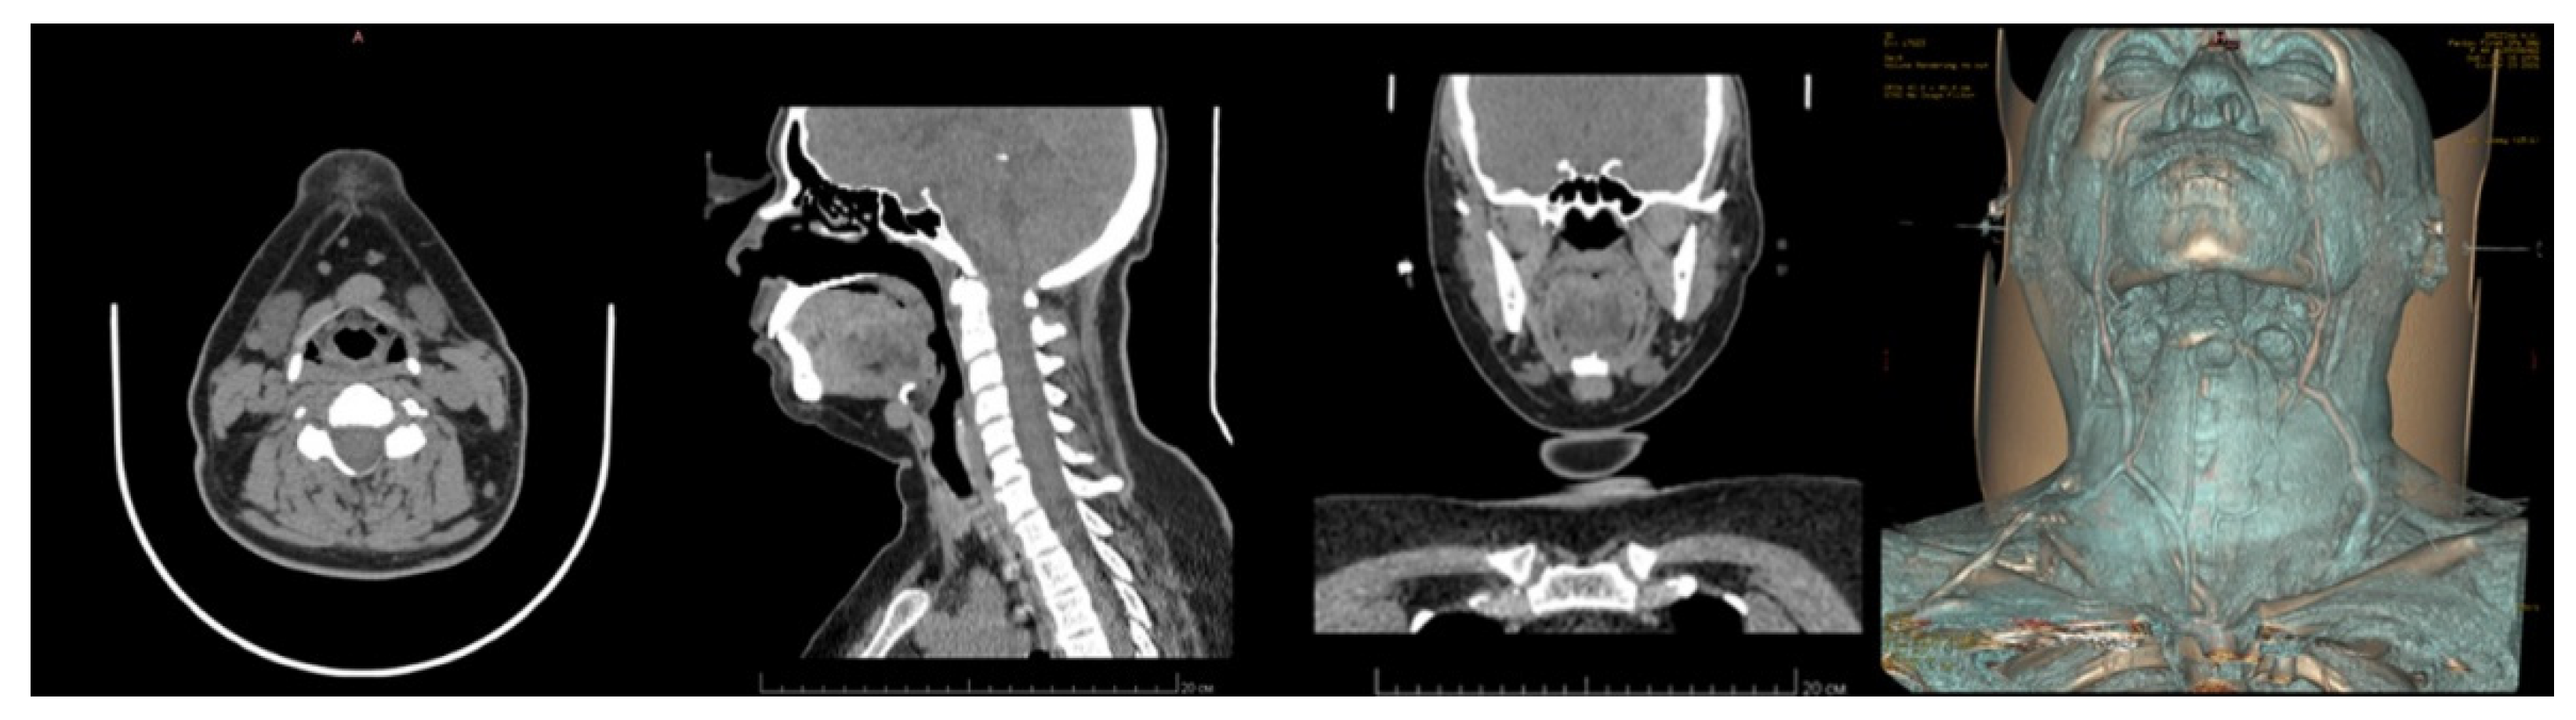

Patient B. was diagnosed with a median neck cyst. During inpatient preoperative treatment in the Maxillofacial Surgery Department, the patient underwent MSCT of the neck, with intravenous contrast enhancement and cystography (Figure 5).

MSCT of the neck: axial view, lateral view, frontal view, and 3D reconstruction.

The MSCT of the neck was performed in the patient’s selected position, similar to the intraoperative one, with a full extension of the cervical spine, using a facial frame made of polyamide and a PLA reference marker.

This solution entailed the use of a special adjustable frame (Patent [23]), which was attached to the patient’s head and adjusted according to the head parameters (Figure 6). It was applied during the CT and was later used again with the customized parameters in the operating room. As a result, the patient’s head was positioned in the same way as during the CT. The hologram positioning was realized by means of a marker installed on the frame (Figure 8). The frame was 3D-printed from polyamide; both the frame and the marker were sterilized.

This approach included not a manual but a semi-automatic adjustment (matching the initial frame coordinates in the virtual space with the CT coordinate system). The frame hade built-in radiopaque markers made of radiodense material in the form of 2 mm × 2 mm metal adjusting screws. These markers allowed the system to match two coordinate systems (Figure 7).

The advantage this method has over the previous one is that it consists of smaller dimensions and that there is no need to produce individual fixation frameworks (Figure 8). In addition, this solution allows for a significant reduction of patient positioning time. Nonetheless, it still requires some preparations to attach the frame to the patient’s head before the surgery.

Figure 8.

Referencing the position of the patient’s head in the operating room using a navigation frame (left). Results of overlaying the 3D model of anatomical structures on the patient, as seen from the mixed reality glasses (right).